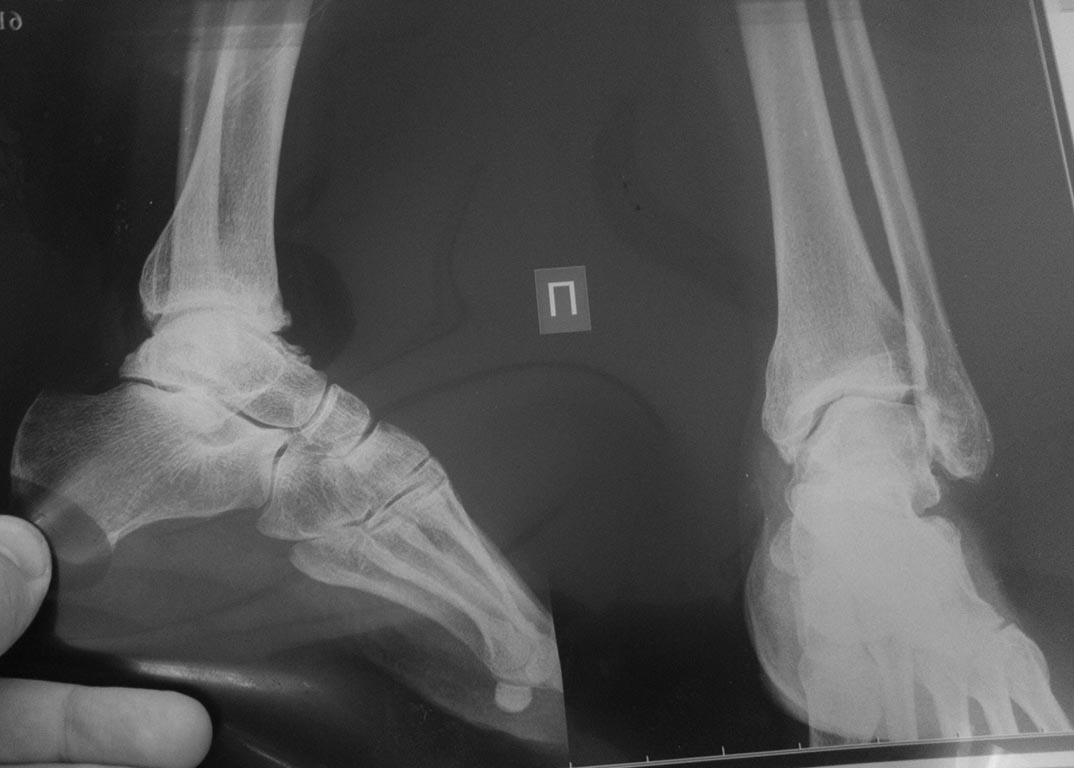

Добрый день!Обратилась женщина 1975 г.р. Жалобы на боль в голеностопном суставе при нагрузке (после ходьбы на расстояние 200 метров).

Травма три года назад. Упала с высоты своего роста, подвернула ногу, лечилась амбулаторно с Ds : растяжение связок голеностопного сустава. Rg не делали. После травмы боль осталась, в динамике интенсивность боли прогрессировала. Ухудшение в течении последних 6 мес. Местно : движения в голеностопном суставе в полном обьеме, отек незначительный. Пальпация безболезненна.Rg, Кт прилагается.Какова на ваш взгляд тактика лечения в данном случае?

Интересный случай. А рентген сделан под нагрузкой? Не похоже. Обязательно нужно под нагрузкой сделать. И обещанной КТ что-то не видно. Артроз тут, конечно, есть. Хотя далеко не крайняя степень. Думать об артродезе вроде рановато. Но и какого рада корригирующая остеотомия могла бы помочь тоже по этим снимкам не скажешь.

Изменения не только в голеностопном суставе, но и, мне так кажется, в прилегающих суставах. Процесс не достаточно старый. Может исход приспособительной перестройки на фоне паралитического процесса.

Снимки сделаны без нагрузки. Как будет возможность, выложу Rg с нагрузкой и фото с объемом движений.